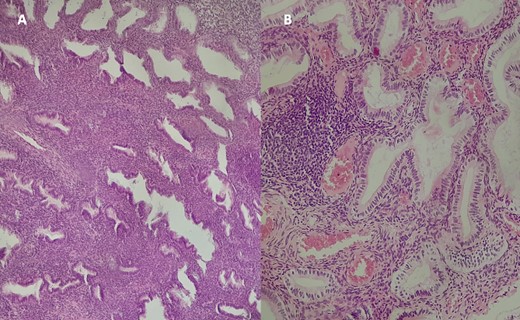

Histological examination of the excised specimen with Hematoxylin–Eosin staining at ×10 magnification (A) and ×40 (B) revealing endometrial glands of variable size and shape, often dilated and cystic, lined by a regular pseudostratified cylindrical epithelium. The stroma is cytogenetic with hemorrhagic changes, without signs of dysplasia or malignancy.